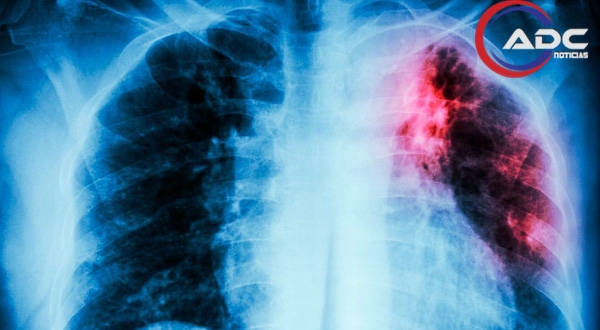

La tuberculosis, causada por una bacteria que afecta principalmente los pulmones, se transmite por el aire cuando una persona enferma tose o estornuda. De acuerdo con organismos internacionales de salud, miles de personas mueren cada año por esta enfermedad, pese a que es prevenible y curable si se detecta a tiempo y se sigue un tratamiento adecuado.